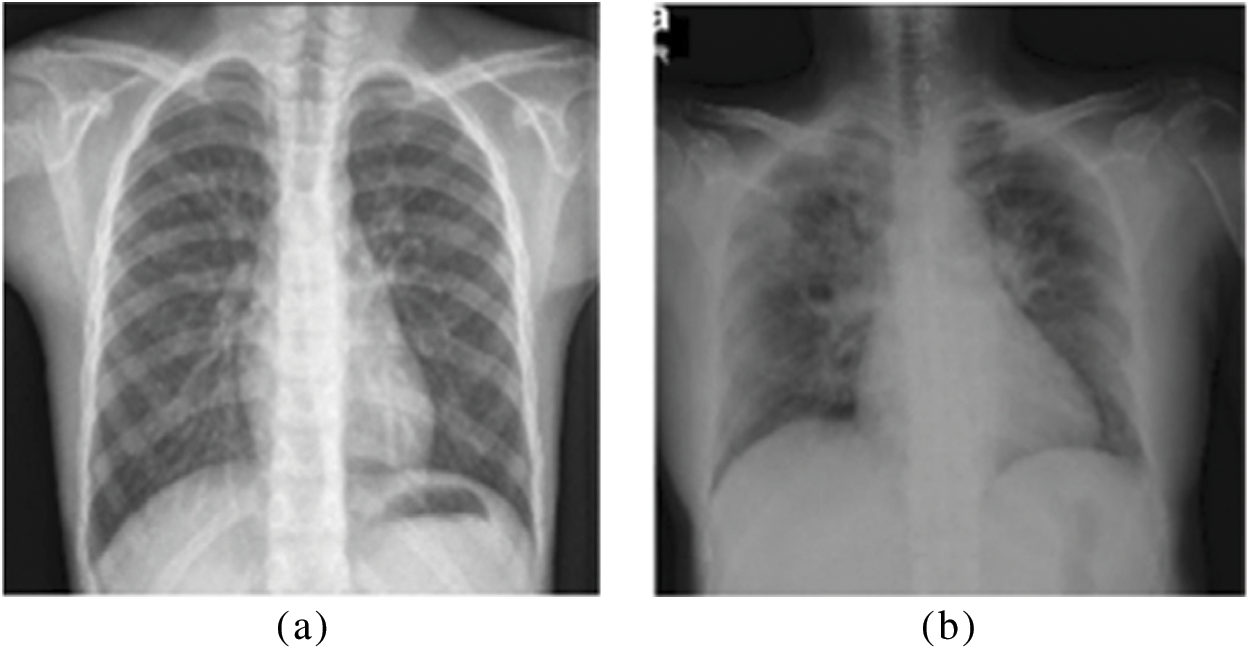

The employed dataset of this work is collected by various researchers from Qatar University, Doha, Qatar, and the University of Dhaka, Bangladesh, along with a team of doctors. The dataset comprises chest X-ray images of covid19 positive patients, along with normal cases. The total number of images is 2850. Out of which 1468 images are positive COVID-19 cases, and 1382 are normal cases. To boost the performance of the proposed model, this dataset is augmented by randomly applying various transformation operations. The size of the dataset after augmentation is 8550 images. Fig. 3 shows sample images from the dataset for normal and COVID-19 cases.

Figure 3: Sample CXR images in the dataset (a) Normal image (b) Covid19 Image